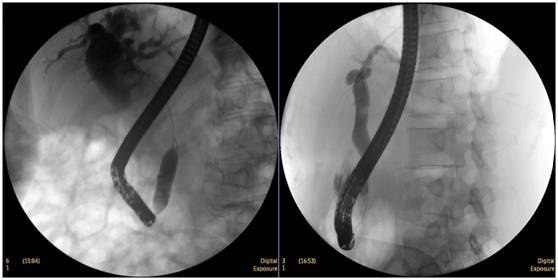

柱狀球囊擴張完全,膽總管擴張,下段見充盈缺損影。

膽總管擴張,下段見明顯充盈缺損(上圖為反片且局部放大后效果)

柱狀球囊擴張膽總管下段及乳頭(上圖為使用取石網籃取石)。